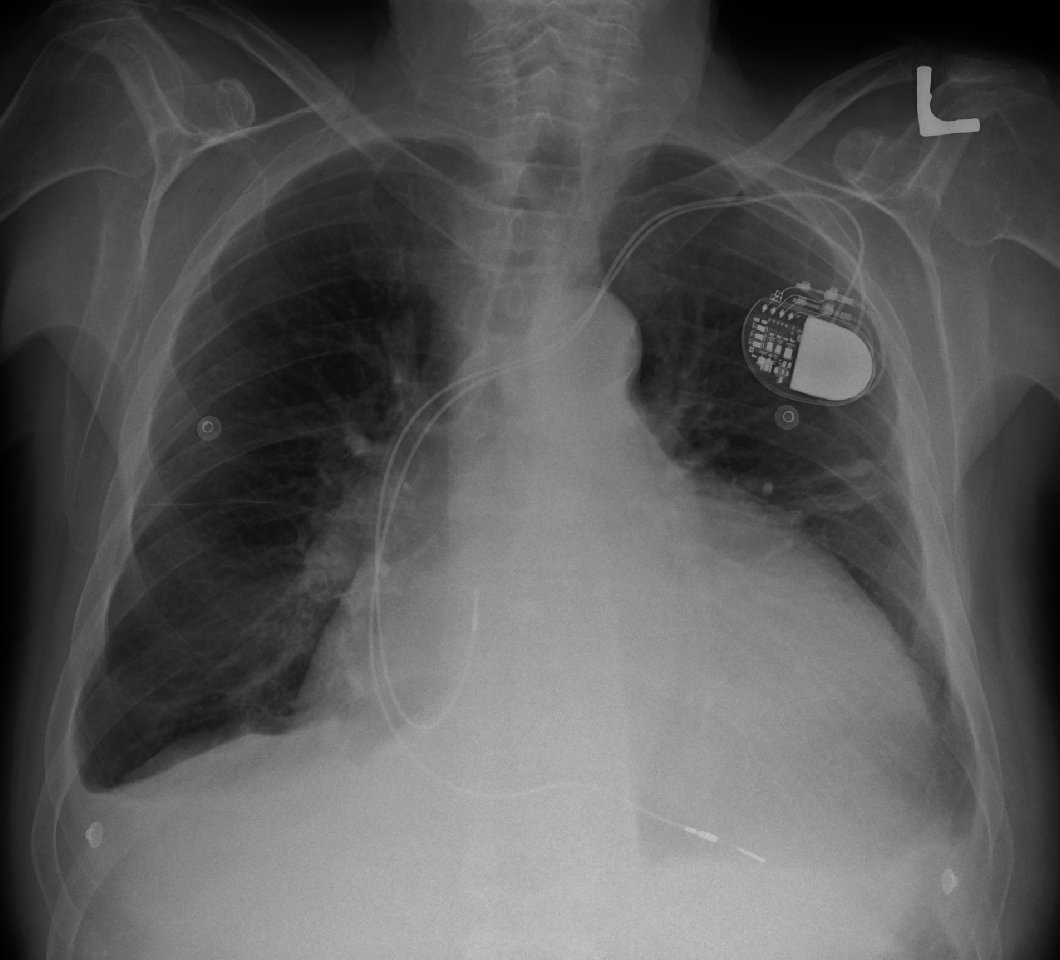

Devices designed to work inside the body, like pacemakers or camera capsules, send data back out of the body, so that doctors can monitor a patient’s health. But that signal, which is transmitted via radio waves, is weak and slow, operating at a maximum of 50 kilobytes per second (for reference, the recommended download speed to properly watch Netflix is 1.5 megabits, or about 188 kilobytes). The FCC requires the devices to have low power, “which inherently limits the communication rates of these devices … to a maximum of 50 kb/s,” according to a new paper.

There could be a downside, though. Anything connected to the internet is vulnerable to hacking, and medical devices are no exception—in fact, last year some experts predicted that hacked medical devices would provide the biggest cybersecurity risk this year. If devices are going to send data via ultrasound, researchers might just have to make sure they encrypt that data. Luckily, a few years ago researchers figured out how to do that. It’s safe to figure the bandwidth will still be fast enough if all the data is also encrypted.